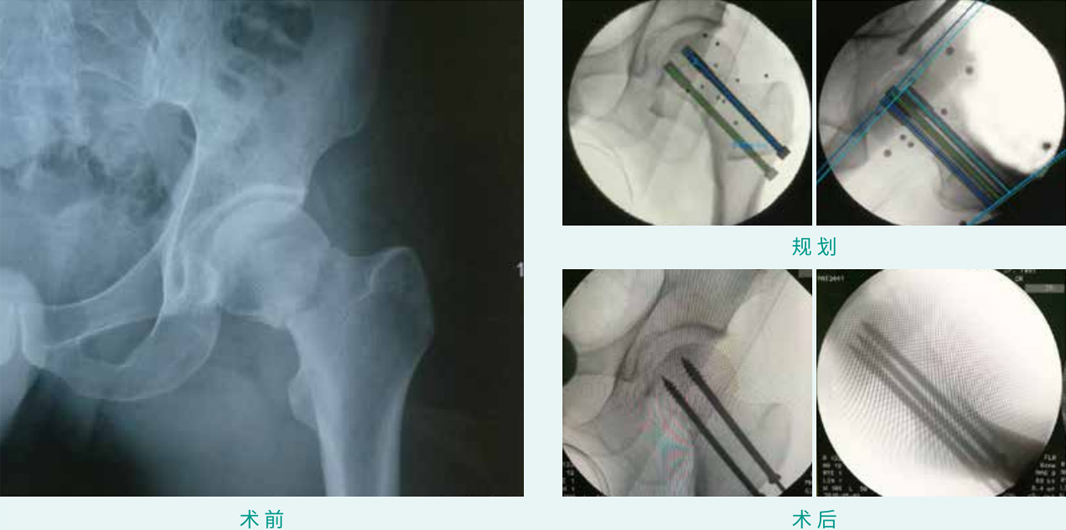

天玑? 辅助股骨颈骨折经皮空心螺钉内牢靠术

基本情形:患者男,,,,,,38岁,,,,,,股骨颈骨折

机械人累积用时:15分钟

植入物:3枚空心螺钉

病例泉源:安徽省医科大学第一隶属医院 张琦